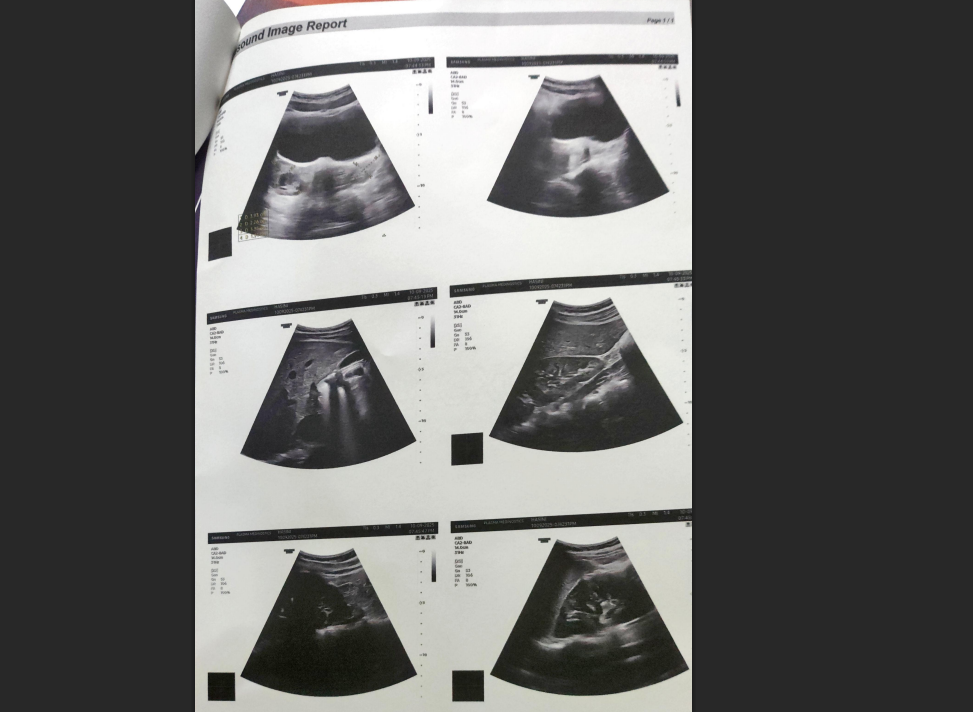

The first thing we did was go through Harini’s reports carefully, not just the ultrasound, but the full picture.

Her ultrasound showed a polycystic ovarian pattern bilaterally: the characteristic finding associated with PCOS.

But what the ultrasound alone doesn’t tell you is why the body is presenting this way. For that, we needed to look deeper.